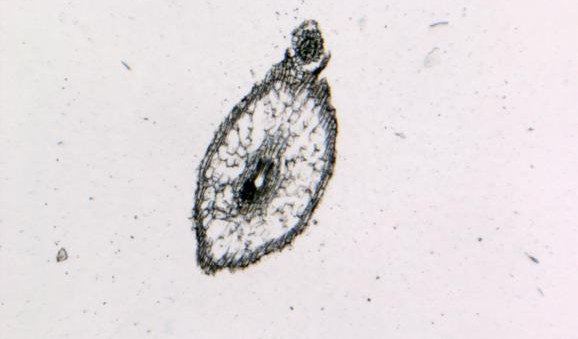

病理平臺(tái)可承接:石蠟切片,切片掃描,熒光掃描,HE染色,各種特殊染色,如:Masson、油紅O、PAS、番紅O、ALP、TRAP、甲苯胺藍(lán)以及免疫組化/熒光、原位雜交等,3D HISTECH滿足對(duì)結(jié)果高質(zhì)量,高標(biāo)準(zhǔn),周期快的實(shí)驗(yàn)外包需求,并提供染色培訓(xùn)服務(wù),分線上視頻,線下實(shí)操帶教兩種培訓(xùn)方案。